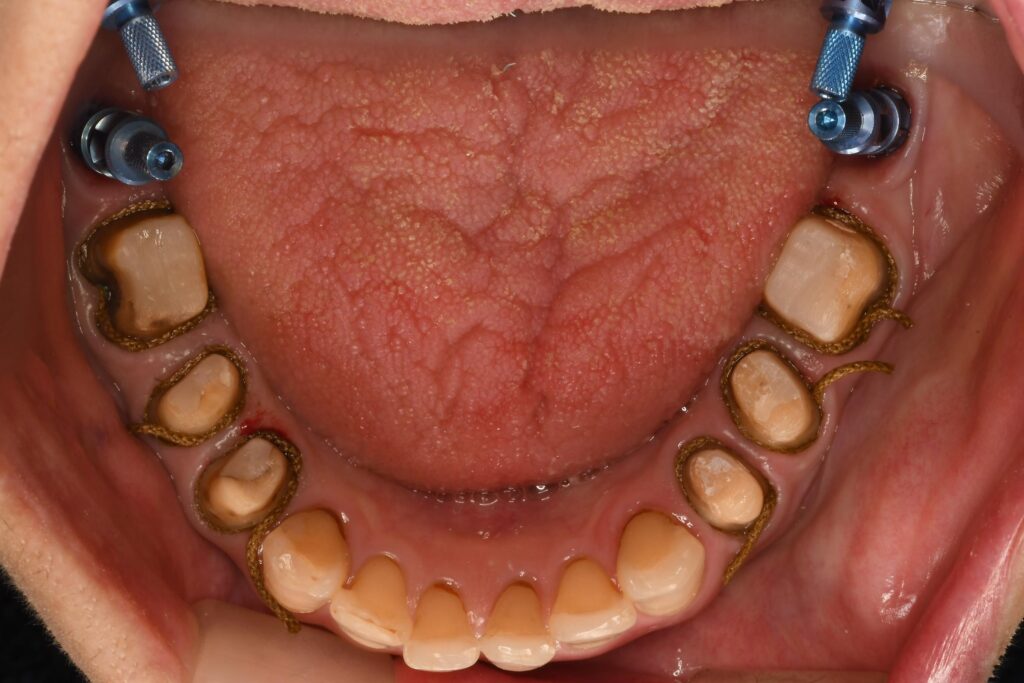

右下6番の痛み・歯ぐきの腫れで来院された方の治療(根管治療)【保険診療】

「右下の奥歯が痛い」「歯ぐきが腫れている」という症状でご来院された患者さんの治療内容をご紹介します。 初診時、右…

右上奥歯の銀歯が取れた方の「即日・短時間」修復を行いました

本日、「右上の奥歯の銀歯が取れた」とのことで、ご来院された患者さんがいらっしゃいました。 外れてしまった部位を確…